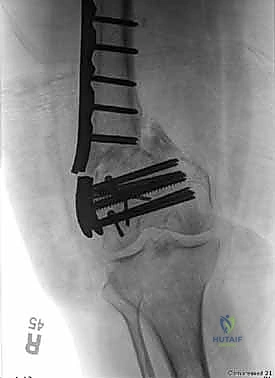

المرحلة الرابعة: التثبيت النهائي بالشرائح والمسامير (Fixation)

يتم استخدام "شرائح الإغلاق التشريحية" (Anatomical Locking Plates) المصنوعة من التيتانيوم عالي الجودة. هذه الشرائح مصممة خصيصاً لتأخذ شكل الجزء السفلي من عظم الفخذ. يتم تمرير الشريحة أسفل العضلات وتثبيتها بمسامير تغلق داخل الشريحة نفسها (Locking Screws)، مما يوفر ثباتاً ميكانيكياً هائلاً، حتى في حالات العظام الهشة.

في بعض الحالات المعقدة جداً، قد يتطلب الأمر استخدام شريحتين (Dual Plating) لضمان عدم تحرك الكسر أثناء فترة التعافي.

المرحلة الخامسة: الإغلاق التجميلي

بعد التأكد التام من استقرار الكسر وحركة المفصل عن طريق الأشعة داخل غرفة العمليات، يتم إغلاق الجرح بطبقات متعددة باستخدام خيوط تجميلية لتقليل الندبات، ووضع أنبوب تصريف (Drain) لمنع تجمع الدم.